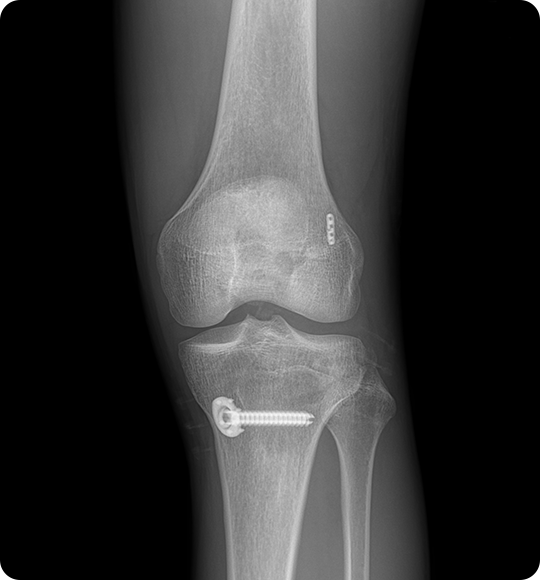

전방십자인대 수술

십자인대 재건술

이 수술은 끊어진 인대를 봉합하는 것이 아니라

자가건(햄스트링건, 슬개건 등) 또는

인공건을 이용해 새로운 인대를 이식하게 되며,

재건을 통해 통증을 줄이고 무릎 기능을 되살립니다.

십자인대재건술 치료과정

인대를 뼈에 단단히 고정 후,

관절 내 위치와 장력을

확인하고 봉합합니다.